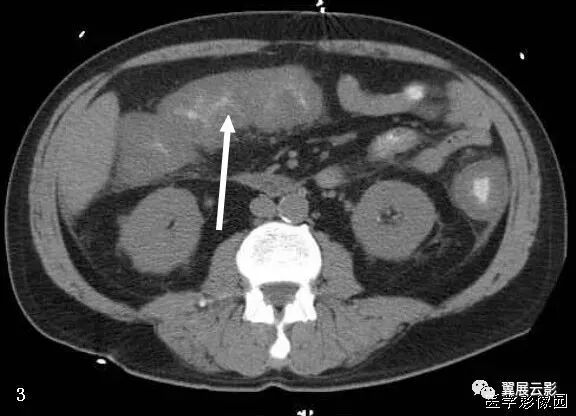

15、梳齿征

腹盆腔C扫描时,于回肠的系膜侧可见多个直管状,扭曲的阴影排列成梳齿状。

供应小肠的动脉由肠系膜上下动脉发出,于肠系膜内形成一系列相互吻合呈弓状的小肠动脉支。其终末分支(直小动脉)在空肠比较长且相巨间距离较大,而在回肠则比较短相对距离较近。冈此,当回肠系膜内的直小动脉增多、扭曲、扩张,相互间距离增大时,在CT增强扫描时表现为梳齿状,称为梳齿征。这是由于发生炎症性肠病时,受累肠管的血流增多,相应的肠系膜呈纤维脂肪增殖所致,多见克罗恩病。

在克罗恩病中肠系膜经常受累。克罗恩病常常累及肠系膜而致纤维脂肪样增殖,也称为肠系膜脂肪蔓延,这是导致小肠检查中出现肠襻分离的主要原因。小肠和肠系膜之间的脂肪界面消失,由于发生炎症改变使脂肪密度升高20~60Hu。肠系膜的纤维脂肪浸润仅是形成梳齿征的部分原因,此外更主要的原因是血管从所在肠管的浆膜面分离,在CT扫描时血管直立突出并彼此分离而形成梳齿状。同时在CT上还可以见到淋巴结肿大,通常大小为3~8mm,如果淋巴结肿大>10mm,则要排除发生淋巴瘤(或癌),因为这两种病在克罗恩病患者中的发生率要高于普通人群。

在已知患有克罗恩病的患者中,如果出现了上述由肠系膜血管增生、扭曲、扩张,以及因直小血管的突出而形成的梳齿征时,表明疾病有急性恶化的趋势,有文献报道克罗恩病患者肠周血管显著提示疾病活动、进展或广泛蔓延。

口服造影剂和静脉增强CT扫描显示过度形成的血管和直血管充血(箭头)。

病例a:冠状位重建显示肠系膜血管增多、密集,呈梳齿征。

病例b:冠状面MIP重建,肠系膜血管增多、密集,呈梳齿状排列,亦可见增厚肠壁。